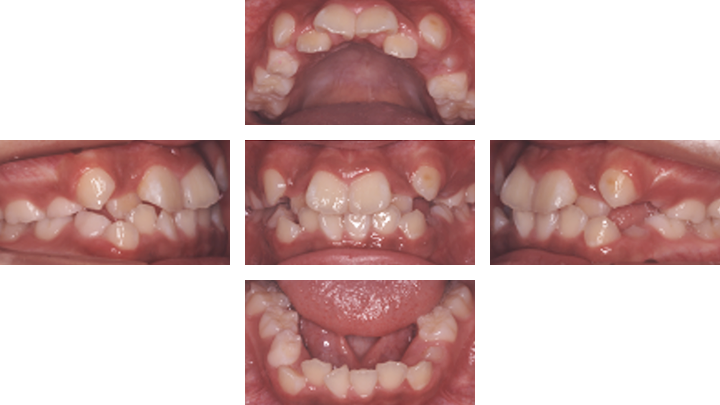

叢生case1. 10代女性(治療期間3年3か月)| 主訴 | ①歯並びが悪い(審美障害)②歯みがきがしづらい |

|---|---|

| 診断名 | 叢生 |

| 初診時年齢 | 11歳4か月 |

| 性別 | 女性 |

| 動的治療期間 | 3年3か月 |

| 主な矯正装置 | リンガルアーチ、セクショナルアーチ、マルチブラケット装置 |

| 抜歯/非抜歯 | 上下顎両側4番(連続抜去) |

| 治療費用(税込) | 検査診断:44,000円 装置料:440,000円 調節料:5,500円×38回 |

| 副作用とリスク | 固定式の矯正装置は歯みがきがしにくいためにむし歯や歯肉炎になりやすい。また、話しづらくなったり食べづらくなったりします。 |

治療前

治療後